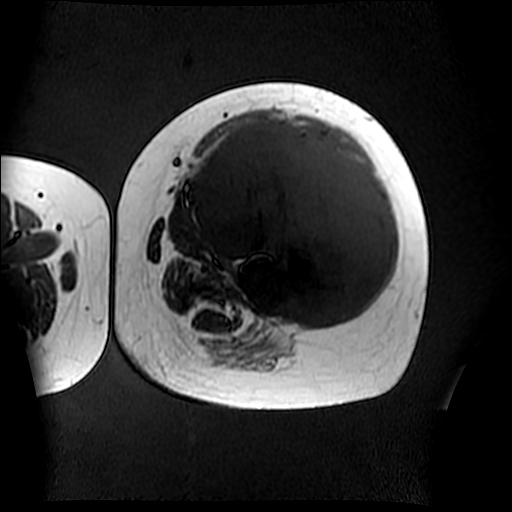

左侧大腿外伤10余年,当时情况不清,发现左侧大腿肿胀7年余,而后又有多次外伤史,近1年来出现疼痛,减重半年。查体:左侧大腿肿胀明显,皮温、肤色正常。

恶性肿瘤,滑膜肉瘤?软骨肉瘤?建议加照平片.

支持左大腿深部间叶组织恶性肿瘤。

恶性肿瘤,滑膜肉瘤,软骨肉瘤

软组织肿块,股骨破坏,增强不均匀强化-----支持恶性肿瘤